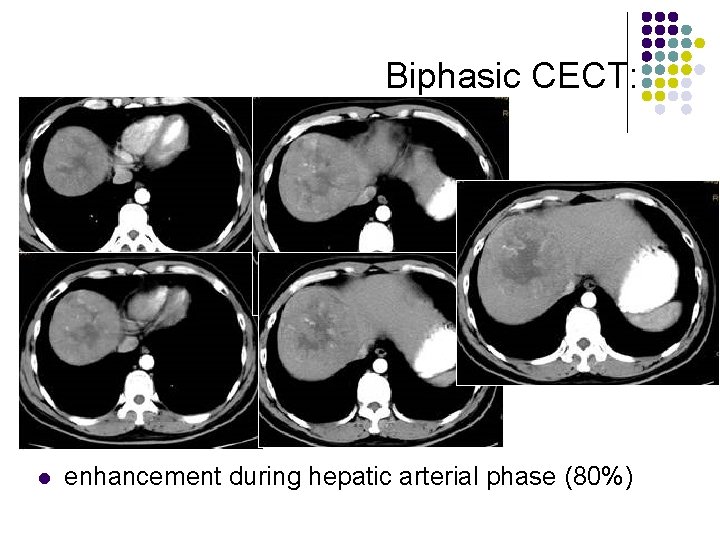

Biphasic CECT: l l l enhancement during hepatic arterial phase (80%) decreased attenuation during portal venous phase with inhomogeneous areas of contrast accumulation isodensity on delayed scans (10%) thin contrast-enhancing capsule (50%) due to rapid washout wedge-shaped areas of decreased attenuation (segmental/lobar perfusion defects due portal vein occlusion by tumor thrombus)

Biphasic CECT: l enhancement during hepatic arterial phase (80%)

Biphasic CECT: l enhancement during hepatic arterial phase (80%)